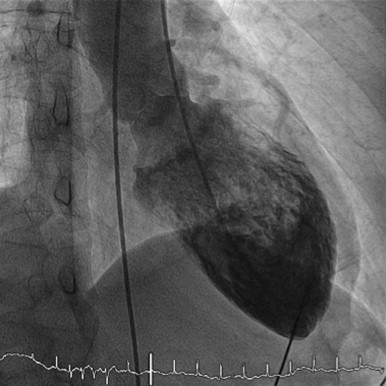

Contributors: Preeya Prakash MD, Adam Greenhaw PharmD, Travis Barlock MD, and Jeffrey Olson MS4 In this episode, cardiologist Preeya Prakash and medical student Jeffrey Olson listen in as two cases are presented from EMM's recent event, Tox Talk 2025. Talk 1- Digoxin Overdose Dr. Adam Greenhaw presents a case of a Digoxin overdose along with many pearls. During the studio listen in, Dr. Prakash helps to answer the questions of: How does digoxin work? Why might a patient still be on digoxin in 2025? What are the EKG findings of digoxin toxicity? Is there any utility in atropine for bradycardia caused by digoxin? Should you use calcium to treat hyperkalemia in the setting of a digoxin overdose? If/when might a cardiologist get involved in a patient with a digoxin overdose? Talk 2- Propranolol Overdose Dr. Travis Barlock presents a case of a beta blocker overdose as well as many associated pearls. During our studio listen in, Dr. Prakash helps to answer the questions of: What are the different beta blockers and how do they work? If you are worried about a propranolol overdose, what medications do you want on hand? What POCUS cardiac view can give you the most information for different scenarios? Why or why not might transcutaneous or intravenous pacing be a good idea for a beta blocker overdose? If/when might you want a cardiologist to get involved in a patient with a beta blocker overdose? References Alahmed AA, Lauffenburger JC, Vaduganathan M, Aldemerdash A, Ting C, Fatani N, Fanikos J, Buckley LF. Contemporary Trends in the Use of and Expenditures on Digoxin in the United States. Am J Cardiovasc Drugs. 2022 Sep;22(5):567-575. doi: 10.1007/s40256-022-00540-x. Epub 2022 Jun 24. PMID: 35739347; PMCID: PMC10263277. Chan BS, Buckley NA. Digoxin-specific antibody fragments in the treatment of digoxin toxicity. Clin Toxicol (Phila). 2014 Sep-Oct;52(8):824-36. doi: 10.3109/15563650.2014.943907. Epub 2014 Aug 4. PMID: 25089630. Hack JB, Wingate S, Zolty R, Rich MW, Hauptman PJ. Expert Consensus on the Diagnosis and Management of Digoxin Toxicity. Am J Med. 2025 Jan;138(1):25-33.e14. doi: 10.1016/j.amjmed.2024.08.018. Epub 2024 Sep 11. PMID: 39265879. Krenz JR, Kaakeh Y. An Overview of Hyperinsulinemic-Euglycemic Therapy in Calcium Channel Blocker and β-blocker Overdose. Pharmacotherapy. 2018 Nov;38(11):1130-1142. doi: 10.1002/phar.2177. Epub 2018 Oct 4. PMID: 30141827. Patocka J, Nepovimova E, Wu W, Kuca K. Digoxin: Pharmacology and toxicology-A review. Environ Toxicol Pharmacol. 2020 Oct;79:103400. doi: 10.1016/j.etap.2020.103400. Epub 2020 May 7. PMID: 32464466. Rotella JA, Greene SL, Koutsogiannis Z, Graudins A, Hung Leang Y, Kuan K, Baxter H, Bourke E, Wong A. Treatment for beta-blocker poisoning: a systematic review. Clin Toxicol (Phila). 2020 Oct;58(10):943-983. doi: 10.1080/15563650.2020.1752918. Epub 2020 Apr 20. PMID: 32310006. Produced by Jeffrey Olson, MS4 Donate: https://emergencymedicalminute.org/donate/